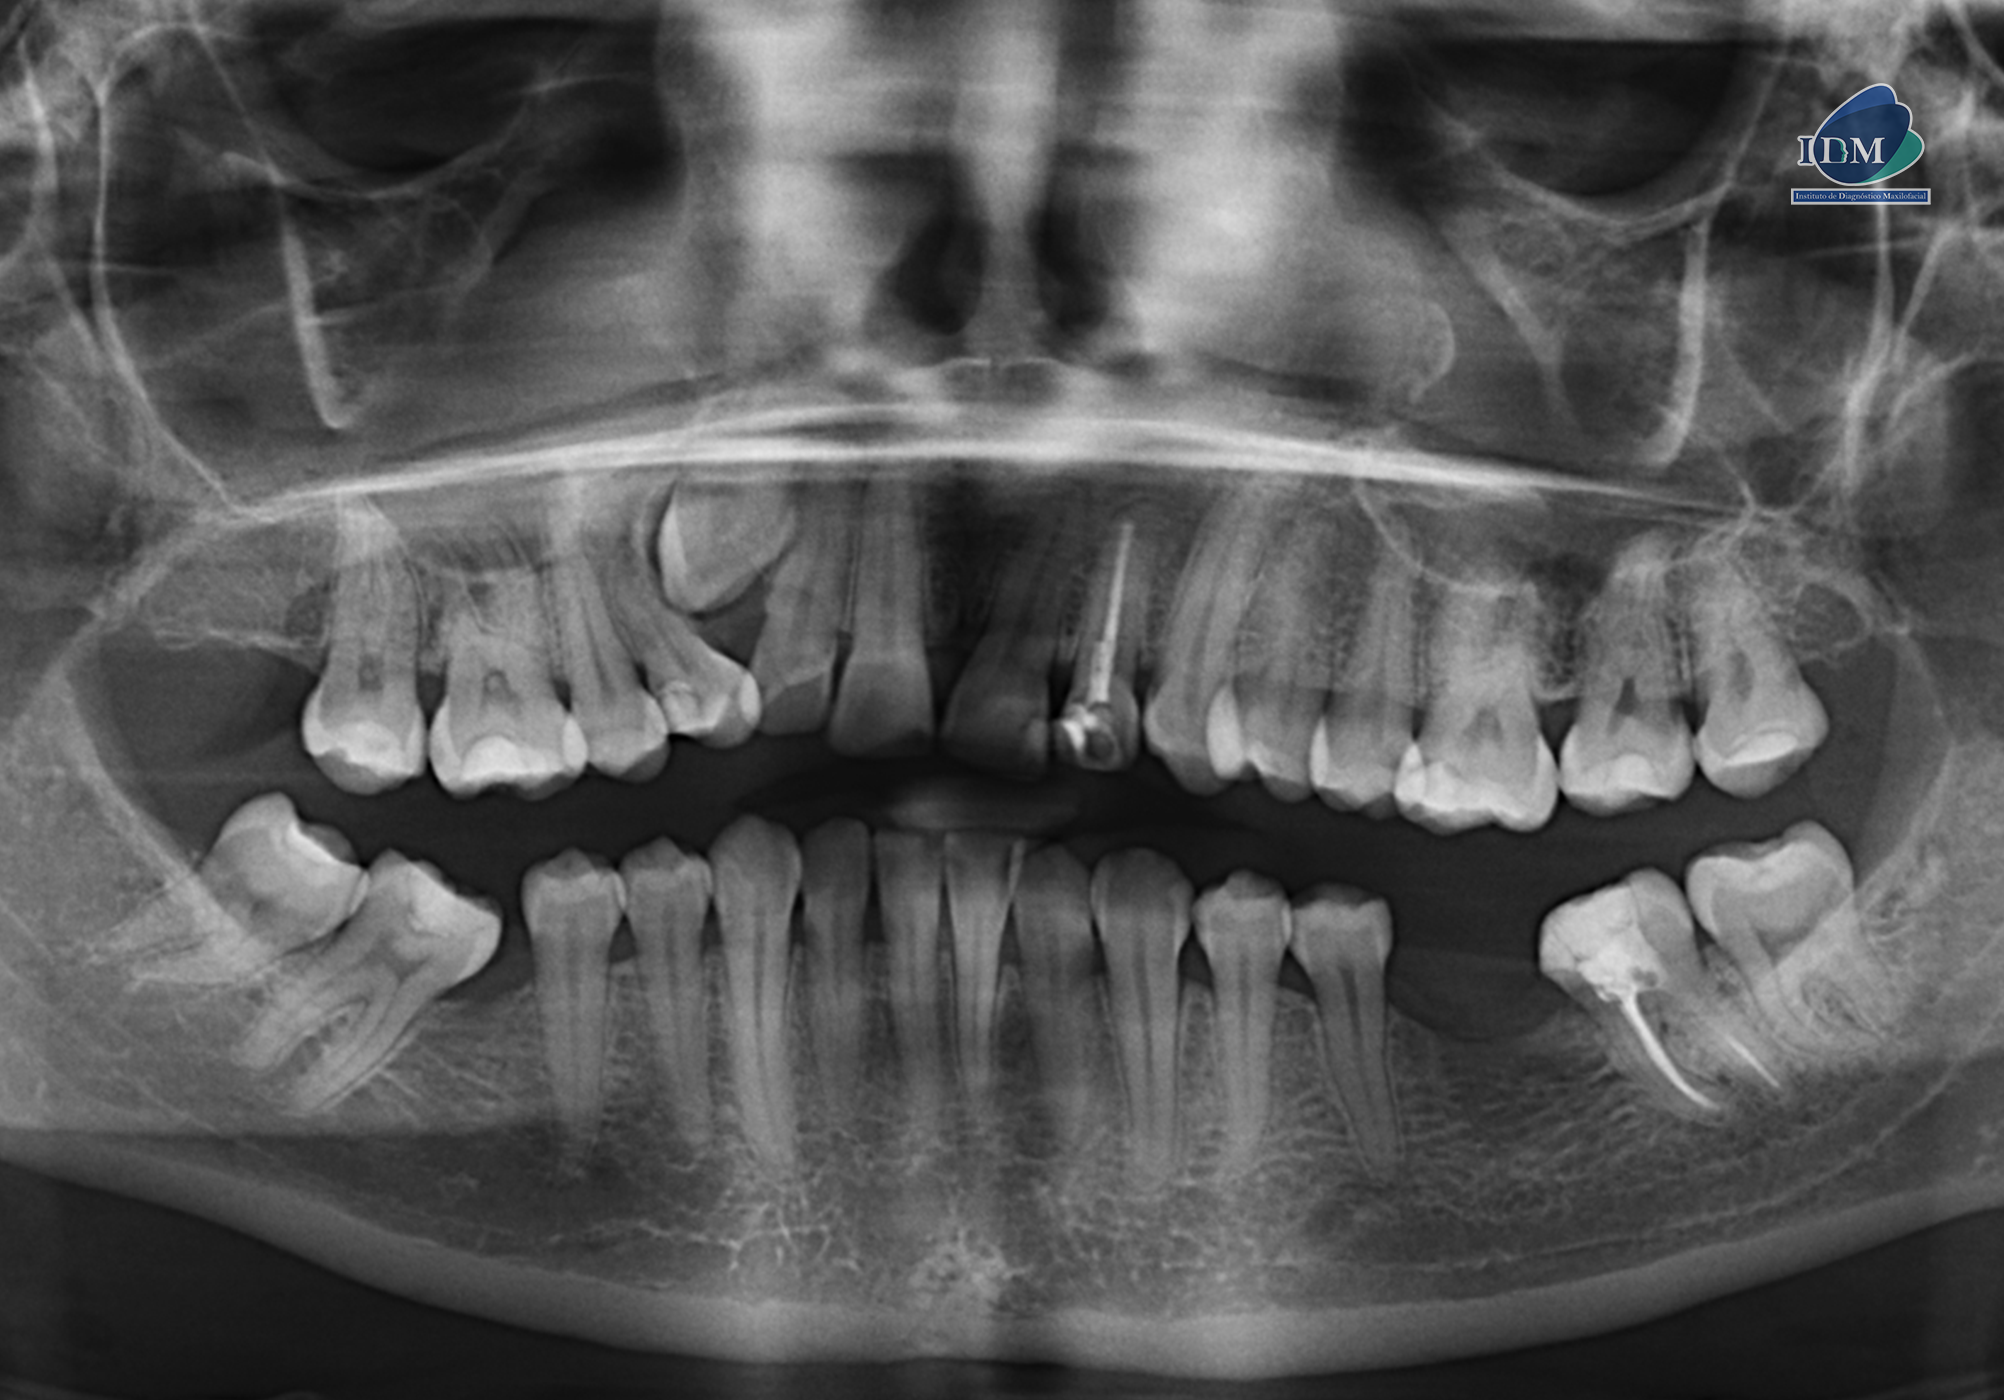

Paciente femenina de 32 años de edad acude al instituto de Diagnóstico maxilofacial – IDM (surco) para evaluación imagenológica de terceros molares.

En la radiografía panorámica (Figura 1), se observa pieza 33 con pérdida del lumen del conducto radicular a nivel del tercio medio y apical.

Radiografia Panorámica

Así mismo en la tomografía volumétrica de haz se evidencia que dicha pieza esta distoangulada con el segmento coronario orientado hacia palatino y el segmento radicular orientado hacia vestibular, conservando el espacio del ligamento periodontal en toda su trayectoria.

- Pieza 1.3 impactada en posición ectópica.